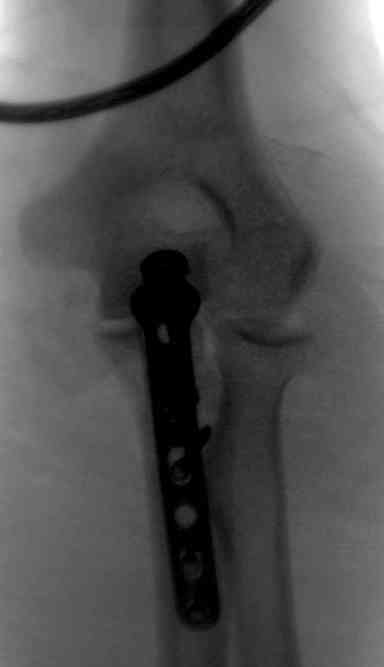

Для фиксации перелома локтевого отростка на сегодня множество

преконтурных с блокирующими возможностями пластин.

Стабильную фиксацию, особенно при оскольчатых переломах, можно добиться,

применяя технику Bridge Plate, и за счет тех пластин, где имеется

возможность проведения множественных шурупов (2.7 мм) проксимально.

Здесь выставлены несколько случаев и варианты фиксации локтевого

отростка, некоторые в комбинации с другими переломами.

1 вариант применен ACUMED локинг пластина

Вложение не в текстовом формате было извлечено…

Имя     : 4 olecranon lat CRM 4.jpg

Тип     : image/jpeg

Размер  : 16857 байтов

Описание: отсутствует

Url     : http://weborto.net:8080/pipermail/ortho/attachments/20071121/9a993135/attachment-0009.jpg